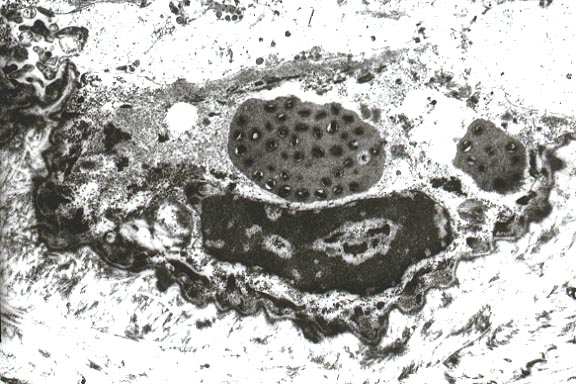

- Case 24-1. Low power view has necrosis and inflammation

of nasal mucosa and thrombosis of nasal vessels. Larger thrombus

demonstrates lines of Zahn (layers of fibrin, wbcs, platelets,

RBCs, etc). Higher power view of vessel wall infiltrated and

replaced by mostly degenerate neutrophils and fibrin. Lines of

Zahn are seen more clearly on the left.